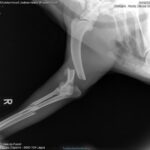

Notfall Pepe, November 2021

Der ca 1 bis 2 jährige Rüde wurde am Freitag (05. Februar 21) von einem Auto erfasst und unversorgt am Straßenrand der N125 in Lagos, Algarve liegen gelassen.

Sein Glück im Unglück: Tierfreunde haben den verletzten Hund im Vorbeifahren trotz Dunkelheit noch gesehen und ihn sofort in die Clínica Veterinária do Ferrel gebracht.

Es hat den armen Kerl übel erwischt, beide Beine auf der gleichen Seite sind je 2 mal gebrochen.

Nach der Erstversorgung hat Frau Dr. Rauterberg sämtliche örtliche Hilfsorganisationen abtelefoniert und um finanzielle Unterstützung

für die anstehenden kostenintensiven Behandlungen/Operationen gebeten.

Die anfallenden Behandlungs- / Operationskosten belaufen sich gesamt geschätzt auf 1.500€- 2.000€.